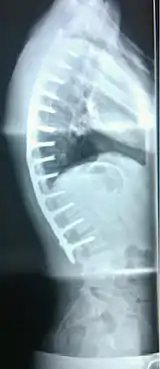

![]() | |

| Scheuermann's disease on lateral Xray of the T spine | |